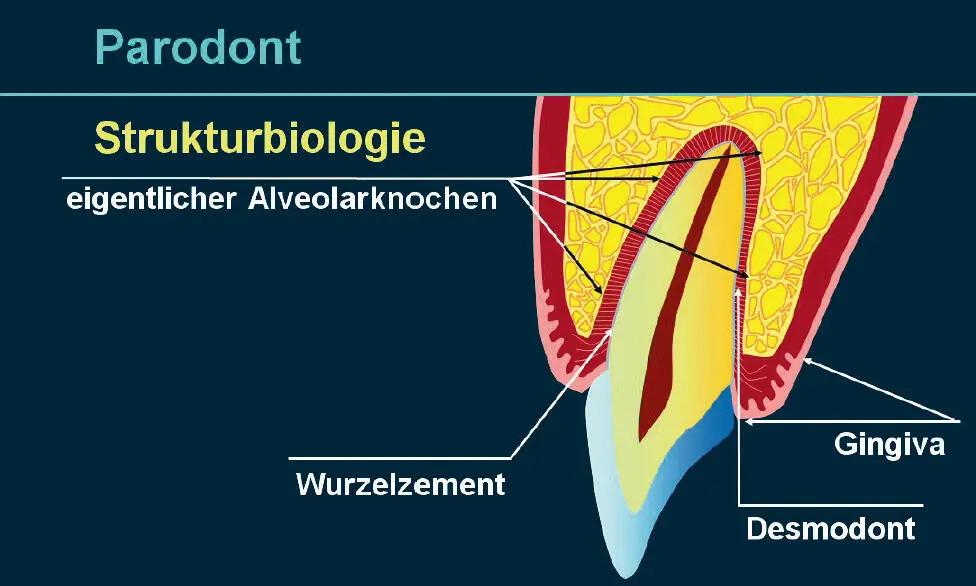

Die Zähne als solche bestehen zum einen aus Schmelz und Dentin und zum anderen aus dem das Pulpakavum ausfüllenden Pulpagewebe. Obwohl das Wurzelzement innig mit dem Dentin und z. T. der Schmelzoberfläche verbunden ist, stellt es definitionsgemäß einen Teil des Parodonts dar. Der Zahnhalteapparat, das Parodont, besteht aus vier Geweben: der Gingiva, dem Desmodont, dem Wurzelzement und dem Alveolarknochen. Der letztere besteht aus dem eigentlichen Alveolarknochen, der mit der Lamina cribriformis der Alveole gleichzusetzen ist, und dem Alveolarfortsatz ( Abb. 1). Desmodont, Wurzelzement und eigentlicher Alveolarknochen entstammen als ektomesenchymale Gewebe dem Zahnsäckchen. Herkunftsmäßig ist Epithelgewebe uneinheitlich, da alle embryonalen Keimblätter in der Lage sind, Epithelgewebe zu bilden. Das Epithel der Mundschleimhaut ist zum Teil ektodermaler (Lippen, Vestibulum, Gingiva, Wangen, Gaumen, Mundboden) und zum Teil entodermaler (Zunge) Herkunft. Das Parodont verfügt über Rezeptoren, die Schmerz, taktile Reize und Druck übertragen. Die Funktion des Parodonts besteht zum einen darin, den Zahn im Kiefer zu verankern und zum anderen das aseptische Ökosystem der inneren Gewebe von der bakteriell kontaminierten Mundhöhle abzuschirmen 1,2.

Abb. 1 Das Parodont als funktionelle Einheit besteht aus vier Geweben: der Gingiva propria, dem Desmodont, dem Wurzelzement und dem eigentlichen Alveolarknochen, der mit der Lamina cribriformis der Alveole gleichzusetzen ist.